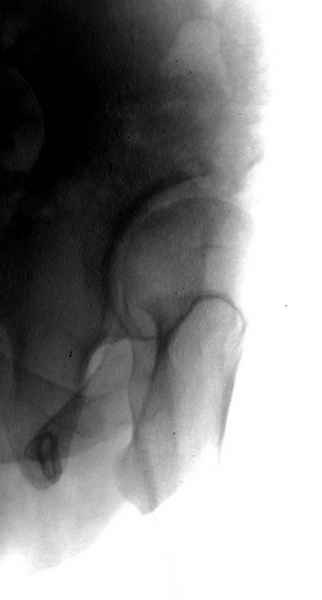

А для данного случая, необходим прямой снимок таза с отдельными суставами, также включить боковые снимки сустава, немаловажно знание покрытия головки спереди.